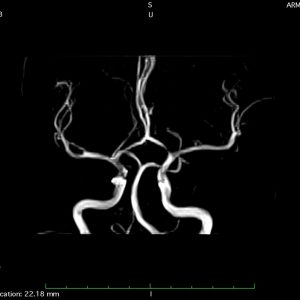

Tim mạch, mạch máu

Tích hợp phần mềm: Tự phát triển, hỗ trợ DICOM, PACS, MIP/MPR 3D